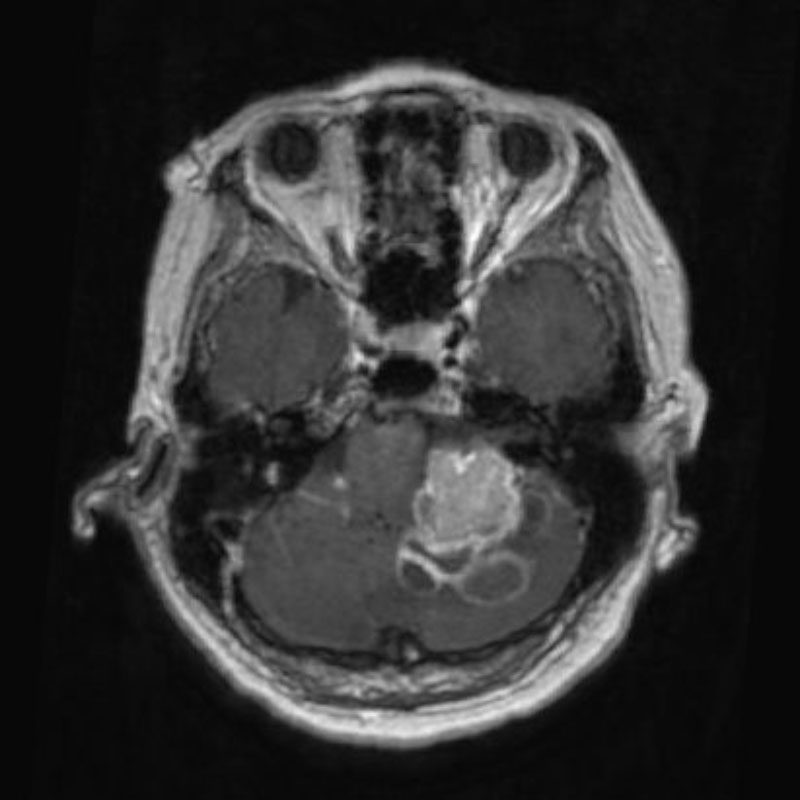

711

'25年12月

60代

良性頭蓋咽頭腫

頭蓋内腫瘍摘出術

No.’25_113 手術前1

No.’25_113 手術前2